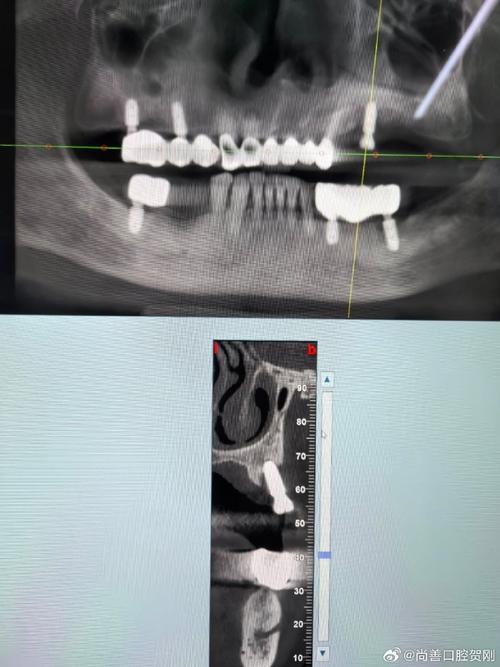

全口牙齿缺失后,牙槽骨会因失去咀嚼刺激而逐渐萎缩,就像长期不用的肌肉会退化一样,牙槽骨骨量不足不仅会导致面部塌陷、显老,还会给种植牙带来挑战——种植体需要植入足够的骨组织内才能稳定,骨量不足时需先进行骨增量手术,缺牙后邻牙可能倾斜、对颌牙伸长,进一步影响修复空间和咬合关系,种牙前必须进行全面检查,包括口腔CBCT(评估骨量、密度、神经血管位置)、牙周健康检查(确保无炎症)、全身健康状况评估(如控制血糖、血压,排除严重骨质疏松等禁忌症)。

术前准备:除了上述检查,还需取模制作手术导板(精准定位种植体位置),与医生沟通修复方案(如牙冠材质、颜色),若有骨量不足,需先进行骨增量手术,如植骨(自体骨、人工骨)、上颌窦提升术(上颌后牙区骨量不足时)等,等待3-6个月骨愈合后再进入下一步。

手术阶段:在局部麻醉或全身麻醉下进行,医生根据导板植入种植体,调整角度和深度以确保初期稳定性,若选择即刻负重,同期安装临时牙冠;若需骨增量,则分阶段手术,术后需注意口腔卫生,避免种植体受力,7-10天拆线。

修复阶段:种植体植入后需3-6个月与骨组织结合(骨结合),期间定期复查,骨结合完成后,安装基台(连接种植体与牙冠的部件),再取模制作永久牙冠(材质有全瓷、烤瓷等,全瓷更美观生物相容性更好),试戴调整咬合后,最终完成修复。